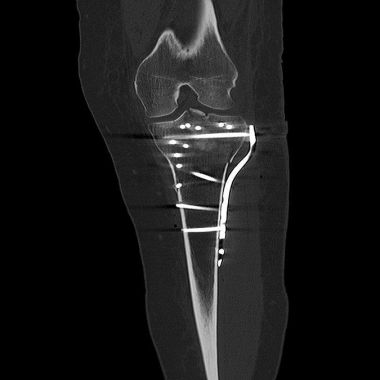

Im Januar 2023 hier operativ versorgte bikondyläre Tibiakopffraktur eines 38 jährigen Familienvaters. Insbesondere die außenseitige hinten liegende Bruchsituation erfordert eine dorsale Plattenlage über einen erweiterten posterolateralen Zugang und intraoperative arthroskopische Kontrolle. Es konnte eine stufenfreie Rekonstruktion und ein nachfolgend sehr schönes funktionelles Ergebnis erzielt werden.